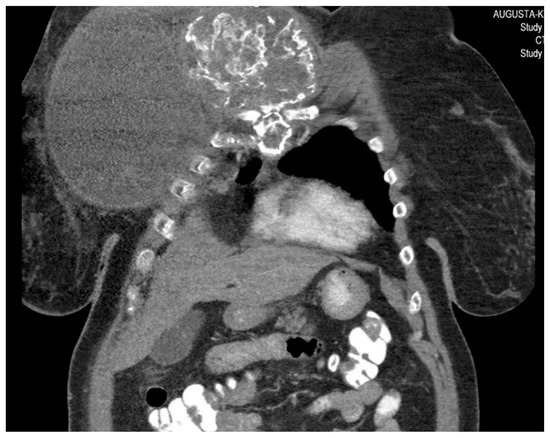

She returned to Bochum in June 2018 with the following symptoms: on the right ventral chest wall, she had a large tumor with a perforation in the pericardium of approximately 15 × 20 cm, an abdominal inguinal tumor on the right, and an ulcerating tumor on the lower left side of the abdomen. A computed tomography of the thorax and abdomen was performed in 09/2018 (Figure 2 and Figure 3) and a magnetic resonance imaging of the thorax was performed in 06/2018 (Figure 4 and Figure 5).

Figure 2.

Computed tomography of thorax and abdomen (CT Thx/Abd) in 2018. In this study, we detected a large tumor on the right anterior thorax with calcifications and invasion in the mediastinum.

Figure 3.

Computed tomography of the thorax and abdomen (CT Thx/Abd) in 2018. There is a large, partially calcified soft tissue structure of the right breast with central hypodensity and possibly mucinous parts. The image shows infiltration of the thoracic wall and transfer to the mediastinum, with destruction of the corpus and manubrium sterni and infiltration of the musculus pecotralis major and the musculus serratus anterior on the right. Additionally, destruction of the adjacent medial clavicle on the right and of the first rib medial on the right was observed. The formation directly infiltrates the mediastinum, with infiltration of the pericardium and direct contact with the aortic arch. The maximum extent of this conglomerate was 25.2 × 14.8 × 10.0 cm (VU 22.7 × 16.6 cm axial; not fully recorded cranially). There was no flow obstruction of the right-side vessels of the upper thoracic aperture.